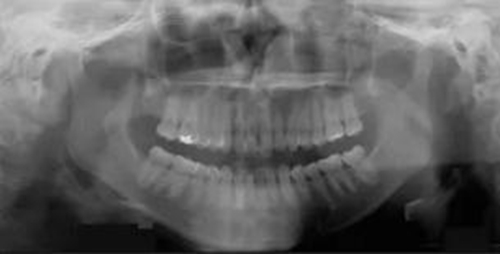

頭側(cè)分析提示為骨性安氏II類(lèi)(ANB,8.4°;Wits,3.6mm),高角(SN-MP,44.9°),上頜切牙略舌傾(U1-SN,96.2°),下頜切牙略舌傾(IMPA,88。3°)(圖2;表)

治療后全景片提示間隙得到關(guān)閉,除了左下頜第一前磨牙外牙根平行度可,無(wú)明顯骨及牙根吸收。(圖7)

治療后頭側(cè)數(shù)據(jù)提示:無(wú)明顯骨性變化(上頜SNA82.1°,下頜SNB74.9°),上頜前牙得到內(nèi)收,略舌傾,頦部前后位置無(wú)明顯改變,仍未凸面型(圖8,表)。將治療前后圖像重疊后結(jié)果如(圖8及圖9),24月后隨訪結(jié)果見(jiàn)圖10.